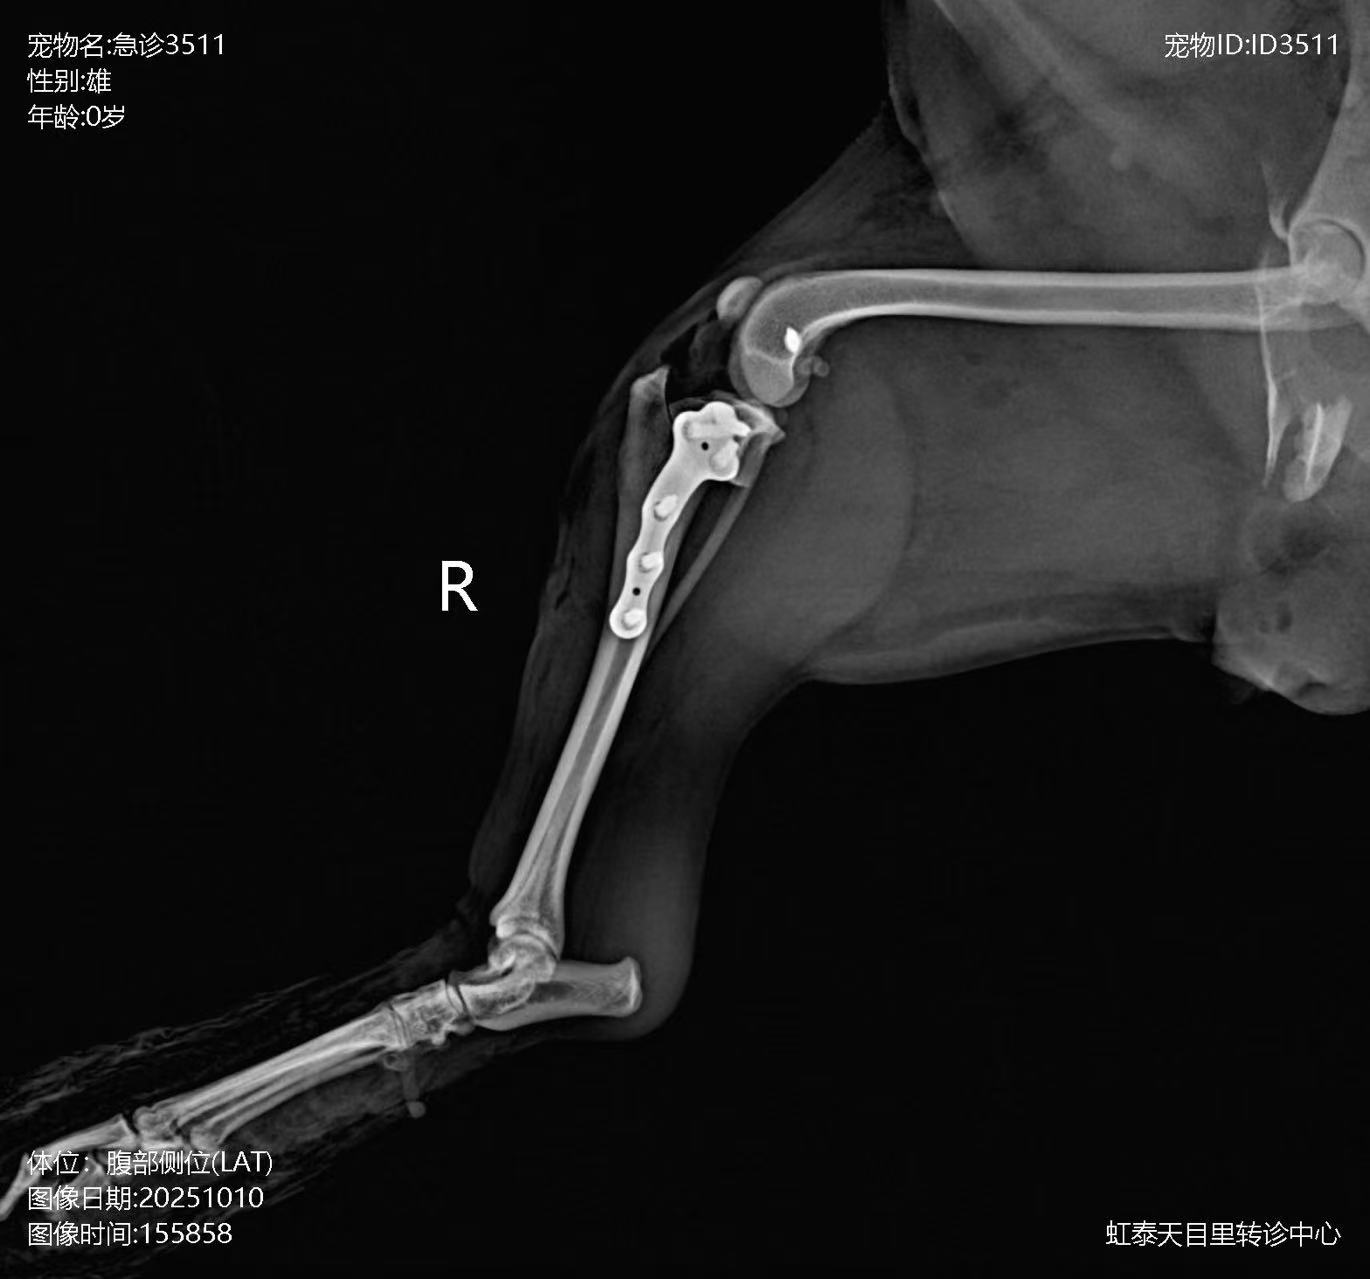

Postoperative X-ray

In this case, the patient suffered a pelvic fracture and multiple ligament ruptures in the knee joint due to a car accident. To address the ligament rupture in the knee, the surgeon used HealFix titanium anchor and a TPLO plate to repair the lateral collateral ligament (LCL) and cranial cruciate ligament (CCL) of the stifle joint.

Repair of stifle joint ligament rupture using HealFix titanium anchor + TPLO plate.